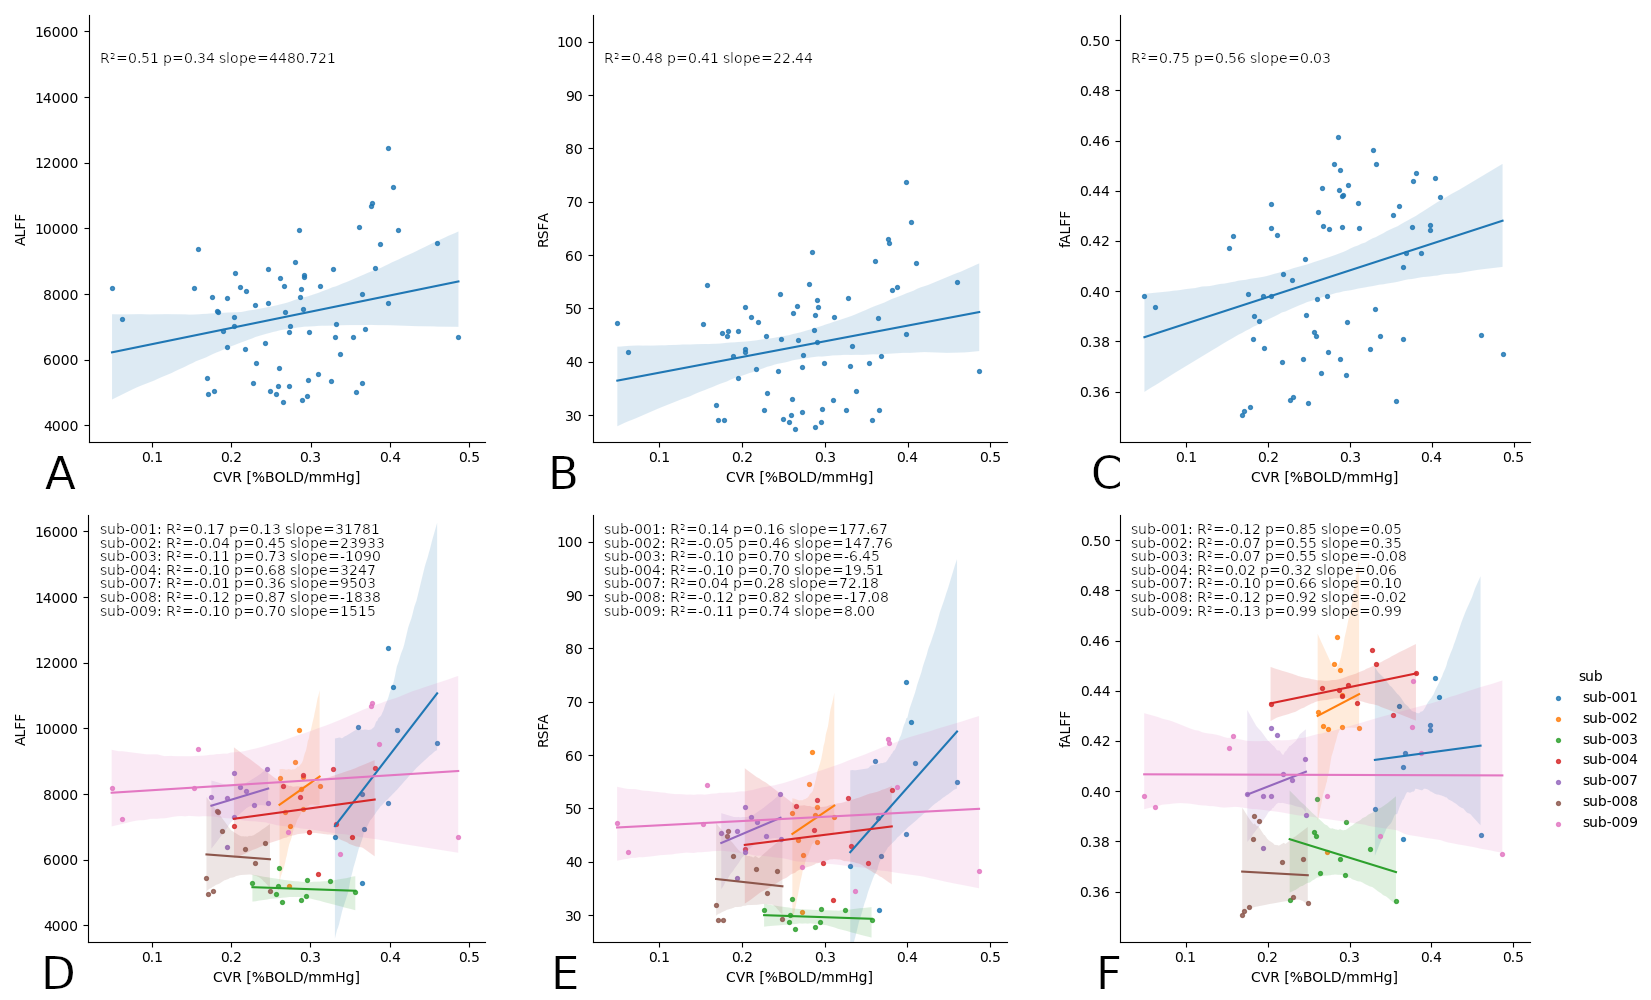

An alternative estimation of CVR (?)

2. Golestani et al. 2016 (NeuroImage)

Estimating CVR with a BH task requires compliant subjects and

dedicated equipment, making it harder to adopt in clinical practice

As a cheaper and feasible alternative, previous literature suggests to use

Resting State fluctuations measures (RSF), such as:

- Resting State Fluctuations Amplitude (RSFA)¹

- [fractional] Amplitude of Low Frequency Fluctuations ([f]ALFF)²

1. Kannurpatti et al. 2014 (PloS ONE)

An alternative estimation of CVR (?)

Data

- The first RS of the session

- A motor task

- A Simon task (executive functions)

We preprocessed RS, motor, and Simon data similarly to CVR

We computed:

- RSFA, ALFF, and fALFF from the first RS session

- task Induced Activation (tIA) of Motor task, as each movement vs sham

- tIA of Simon task, considering congruent or incongruent responses

- RSFA, ALFF, and fALFF from the first RS session

- task Induced Activation (tIA) of Motor task, as each movement vs sham

- tIA of Simon task, considering congruent or incongruent responses

We selected:

Methods: effect of CVR on fMRI

Results were thresholded at \(p<0.05\) after controlling for false discovery rate³

(then at \(p<0.001\) uncorrected)

1. Chen et al. 2013 (Neuroimage); 2. Golestani et al. 2016 (NeuroImage); 3. Benjamini et al. 2006 (Biometrika)

We used 3dLMEr¹ to set up the following LME models voxelwise (R syntax):

- \(RSF \sim cvr + (cvr|session) + (cvr|subject)\)

- \(tIA \sim RSF + (RSF|session) + (RSF|subject)\)

- \(tIA \sim cvr + (cvr|session) + (cvr|subject)\)

We used the first model considering the average GM value of RSF and CVR²

- \(RSF \sim cvr + (cvr|session) + (cvr|subject)\)

- \(tIA \sim RSF + (RSF|session) + (RSF|subject)\)

- \(tIA \sim cvr + (cvr|session) + (cvr|subject)\)

Results: CVR and RSF

Physiology and RSF

We used 3dLMEr¹ to set up the following LME models (R syntax):

Effect of Sex

Only sex had a significant effect on RSF

Effect on CVR

Results: CVR and RSF

Golestani et al. 2016 (NeuroImage)

Results: CVR, RSF, and tasks

Motor task

Simon task, congruent responses

Simon task, incongruent responses

The relationship between CVR, RS fluctuations, and tIA

might be highly subject specific

or absent altogether.

- We did not observe a statistically significant effect of CVR on RS fluctuations, or of CVR and RS fluctuations on task induced activity, most probably due to the high variability between subjects

-

The failure of generalisation of previous observations might be related to different methods, but whether this is related to a better denoising and signal quality or to a possibly non optimal setting (e.g. compared to gas challenges) is uncertain

-

A different statistical perspective (i.e. Bayesian) is required to exclude any relationship between CVR and RS fluctuations, and further analyses are required to improve the agreement between CVR and RS fluctuations